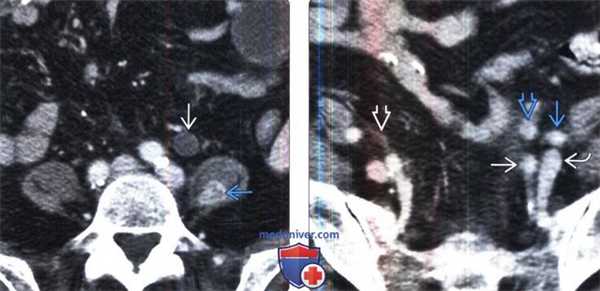

5. Радионуклидная диагностика:

• ПЭТ:

о Гиперметаболические узлы демонстрируют повышенное поглощение ФДГ

о Чувствительность для ПЭТ составляет 90-95% по сравнению с 80-85% для КТ с контрастированием

о Большая чувствительность к лимфомам грудной полости (более 90%), чем брюшной или тазовой полости (более 75%)

о Позволяет увеличить выявление опухолей скрытых локализаций (например, кости, мышцы, отдаленные/не увеличенные узлы):

- Может изменить стадию заболевания в 10-40% случаев

- Изменяет лечение в 25% случаев

о Исследование эффективно для определения раннего ответа на химиотерапию:

- Снижение поглощения ФДГ предшествует уменьшению размеров

о Помогает дифференцировать остаточную лимфому от постлучевого фиброза

о Низкая чувствительность к выявлению В-клеточной лимфомы и мукоза-ассоциированной лимфоидной ткани (MALT)

(Слева) ПЭТ/КТ, аксиальная проекция, этот же пациент: ФДГ-положительная лимфаденопатия при НХЛ.

(Справа) МРТ, Т2-ВИ, SS FSE, аксиальная проекция: у этого же пациента выявлено парааортальное образование , имеющее ИС от высокой до умеренной.